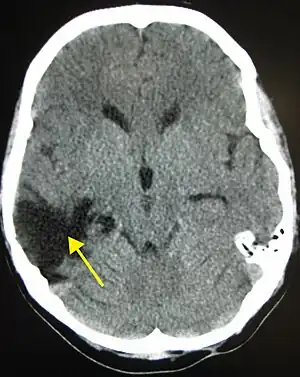

| CT scan showing cerebral contusions, hemorrhage within the hemispheres, and subdural hematoma. There is also displaced skull fracture of left transverse parietal and temporal bones.[2] | |

Hematomas, also focal lesions, are collections of blood in or around the brain that can result from hemorrhage.[24] Intracerebral hemorrhage, with bleeding in the brain tissue itself, is an intra-axial lesion. Extra-axial lesions include epidural hematoma, subdural hematoma, subarachnoid hemorrhage, and intraventricular hemorrhage.[105] Epidural hematoma involves bleeding into the area between the skull and the dura mater, the outermost of the three membranes surrounding the brain.[24] In subdural hematoma, bleeding occurs between the dura and the arachnoid mater.[32] Subarachnoid hemorrhage involves bleeding into the space between the arachnoid membrane and the pia mater.[32] Intraventricular hemorrhage occurs when there is bleeding in the ventricles.[105]